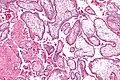

Micrografía que muestra vellosidades coriónicas. Aumento intermedio. Tinción H&E. -

La mayor parte de las vellosidades consiste en tejidos conectivos que contienen vasos sanguíneos. La mayoría de las células del núcleo de tejido conjuntivo de las vellosidades son fibroblastos. También están presentes los macrófagos conocidos como células de Hofbauer .